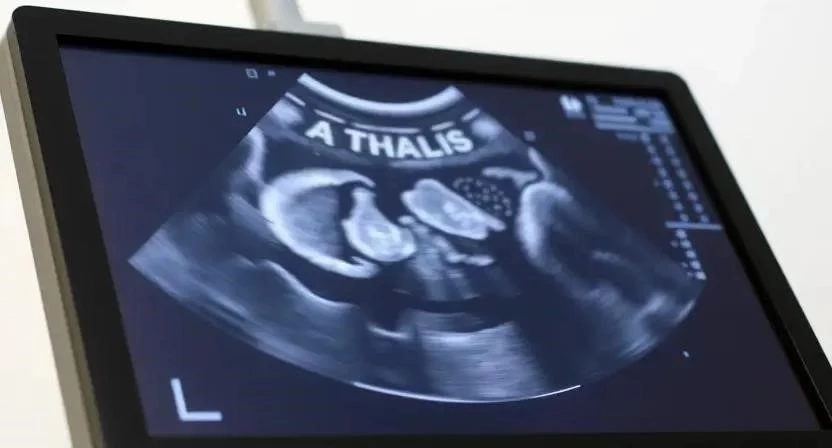

Ультразвуковое исследование (УЗИ)

УЗИ – это безопасный и неинвазивный метод диагностики, который позволяет получить изображение внутренних органов в режиме реального времени. УЗИ широко используется для диагностики заболеваний печени, почек, поджелудочной железы, сердца, а также для выявления беременности и опухолей.

| Подозрение на беременность | Матка |